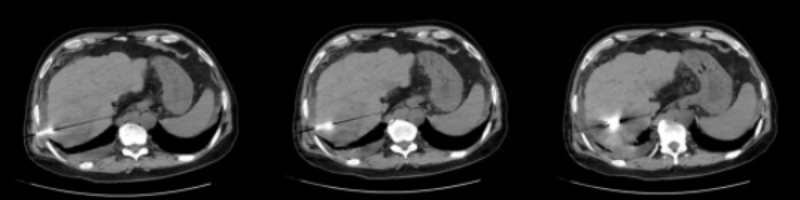

肝腫瘤鄰近橫膈,穿刺難度大,術(shù)前徐穩(wěn)深主任帶領(lǐng)腫瘤科專業(yè)團隊及放射科房志杰醫(yī)生為患者進行精準定位,設定穿刺路線

CT引導下微波消融治療過程